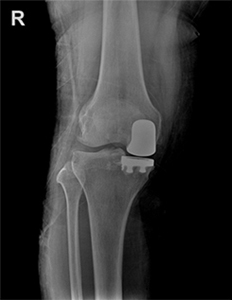

부분 인공관절치환술